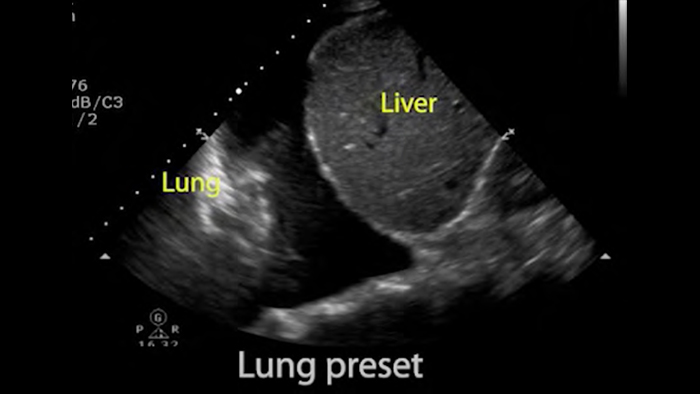

Use Lumify for airway and pulmonary assessment

Lumify POCUS solutions can help you detect the endotracheal tube within the trachea, assist in emergent cricothyrotomy procedures, diagnose pleural effusion and interstitial alveolar diseases.

Pulmonary assessment

Lumify S4-1 broadband phased array transducer

• 4 to 1 MHz extended operating frequency range

• 2D, color Doppler, M-mode, advanced XRES and multivariate harmonic imaging

• High-resolution imaging for abdominal and cardiac applications: Cardiac, OB/GYN, Lung, Abdomen and FAST imaging preset optimizations